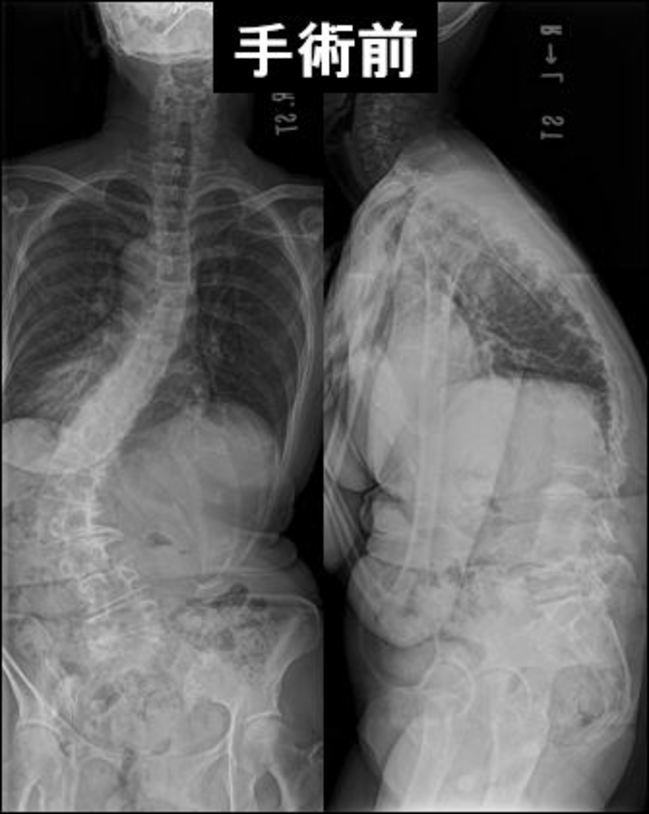

特発性側弯症

未だにその原因は不明ですが、多くの場合思春期に発症・悪化します。 約9割は女の子に発症します。「せぼね」(脊柱)が、ねじれを伴って曲がっています。このため肩の高さやウエストラインの高さに差があらわれ、身体が左右非対称性になってしまいます。お辞儀をしたときの背中や腰の高さにも左右差が出ます。多くは思春期に進行します。40°近くになると服の上からも目立ってきます。

<放置した場合の危険性>

側弯の進行は、通常成長の終了とともに停止しますが、腰椎では30°以上、胸椎では40°以上の場合、成長終了後も進行します。60°を越えると肺活量が低下し、90°だと2分の1、さらに悪化すると肺障害を起こし、死亡の原因となることがあります。曲がりが強くなると上半身と下半身の重心軸がずれ、身体のバランスが崩れることによって歩行障害、腰痛、背部痛等をきたすことがあります。

女性では出産後、授乳期に身体のカルシウムバランスが乱れ、変形が進行します。将来骨粗鬆症が生じた場合、変形がすすみ、日常生活に大きな支障をきたす可能性があります。

<側彎症の治療>

成長終了前で40°未満であれば、装具療法で進行を予防出来ます。ただしこの場合、長時間、長期間の装着が必要です。体操など、他の治療法の効果は科学的に証明されていません。 40°を越えてしまった場合には、美容面と進行予防の目的で手術を行います。